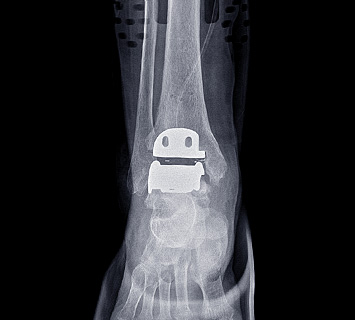

인공관절 수술